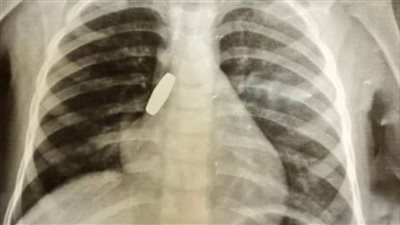

طلقة خرطوش.. الأطباء يكتشفون جسم غريب داخل طفلة

الثلاثاء 19/10/2021 03:57 ص